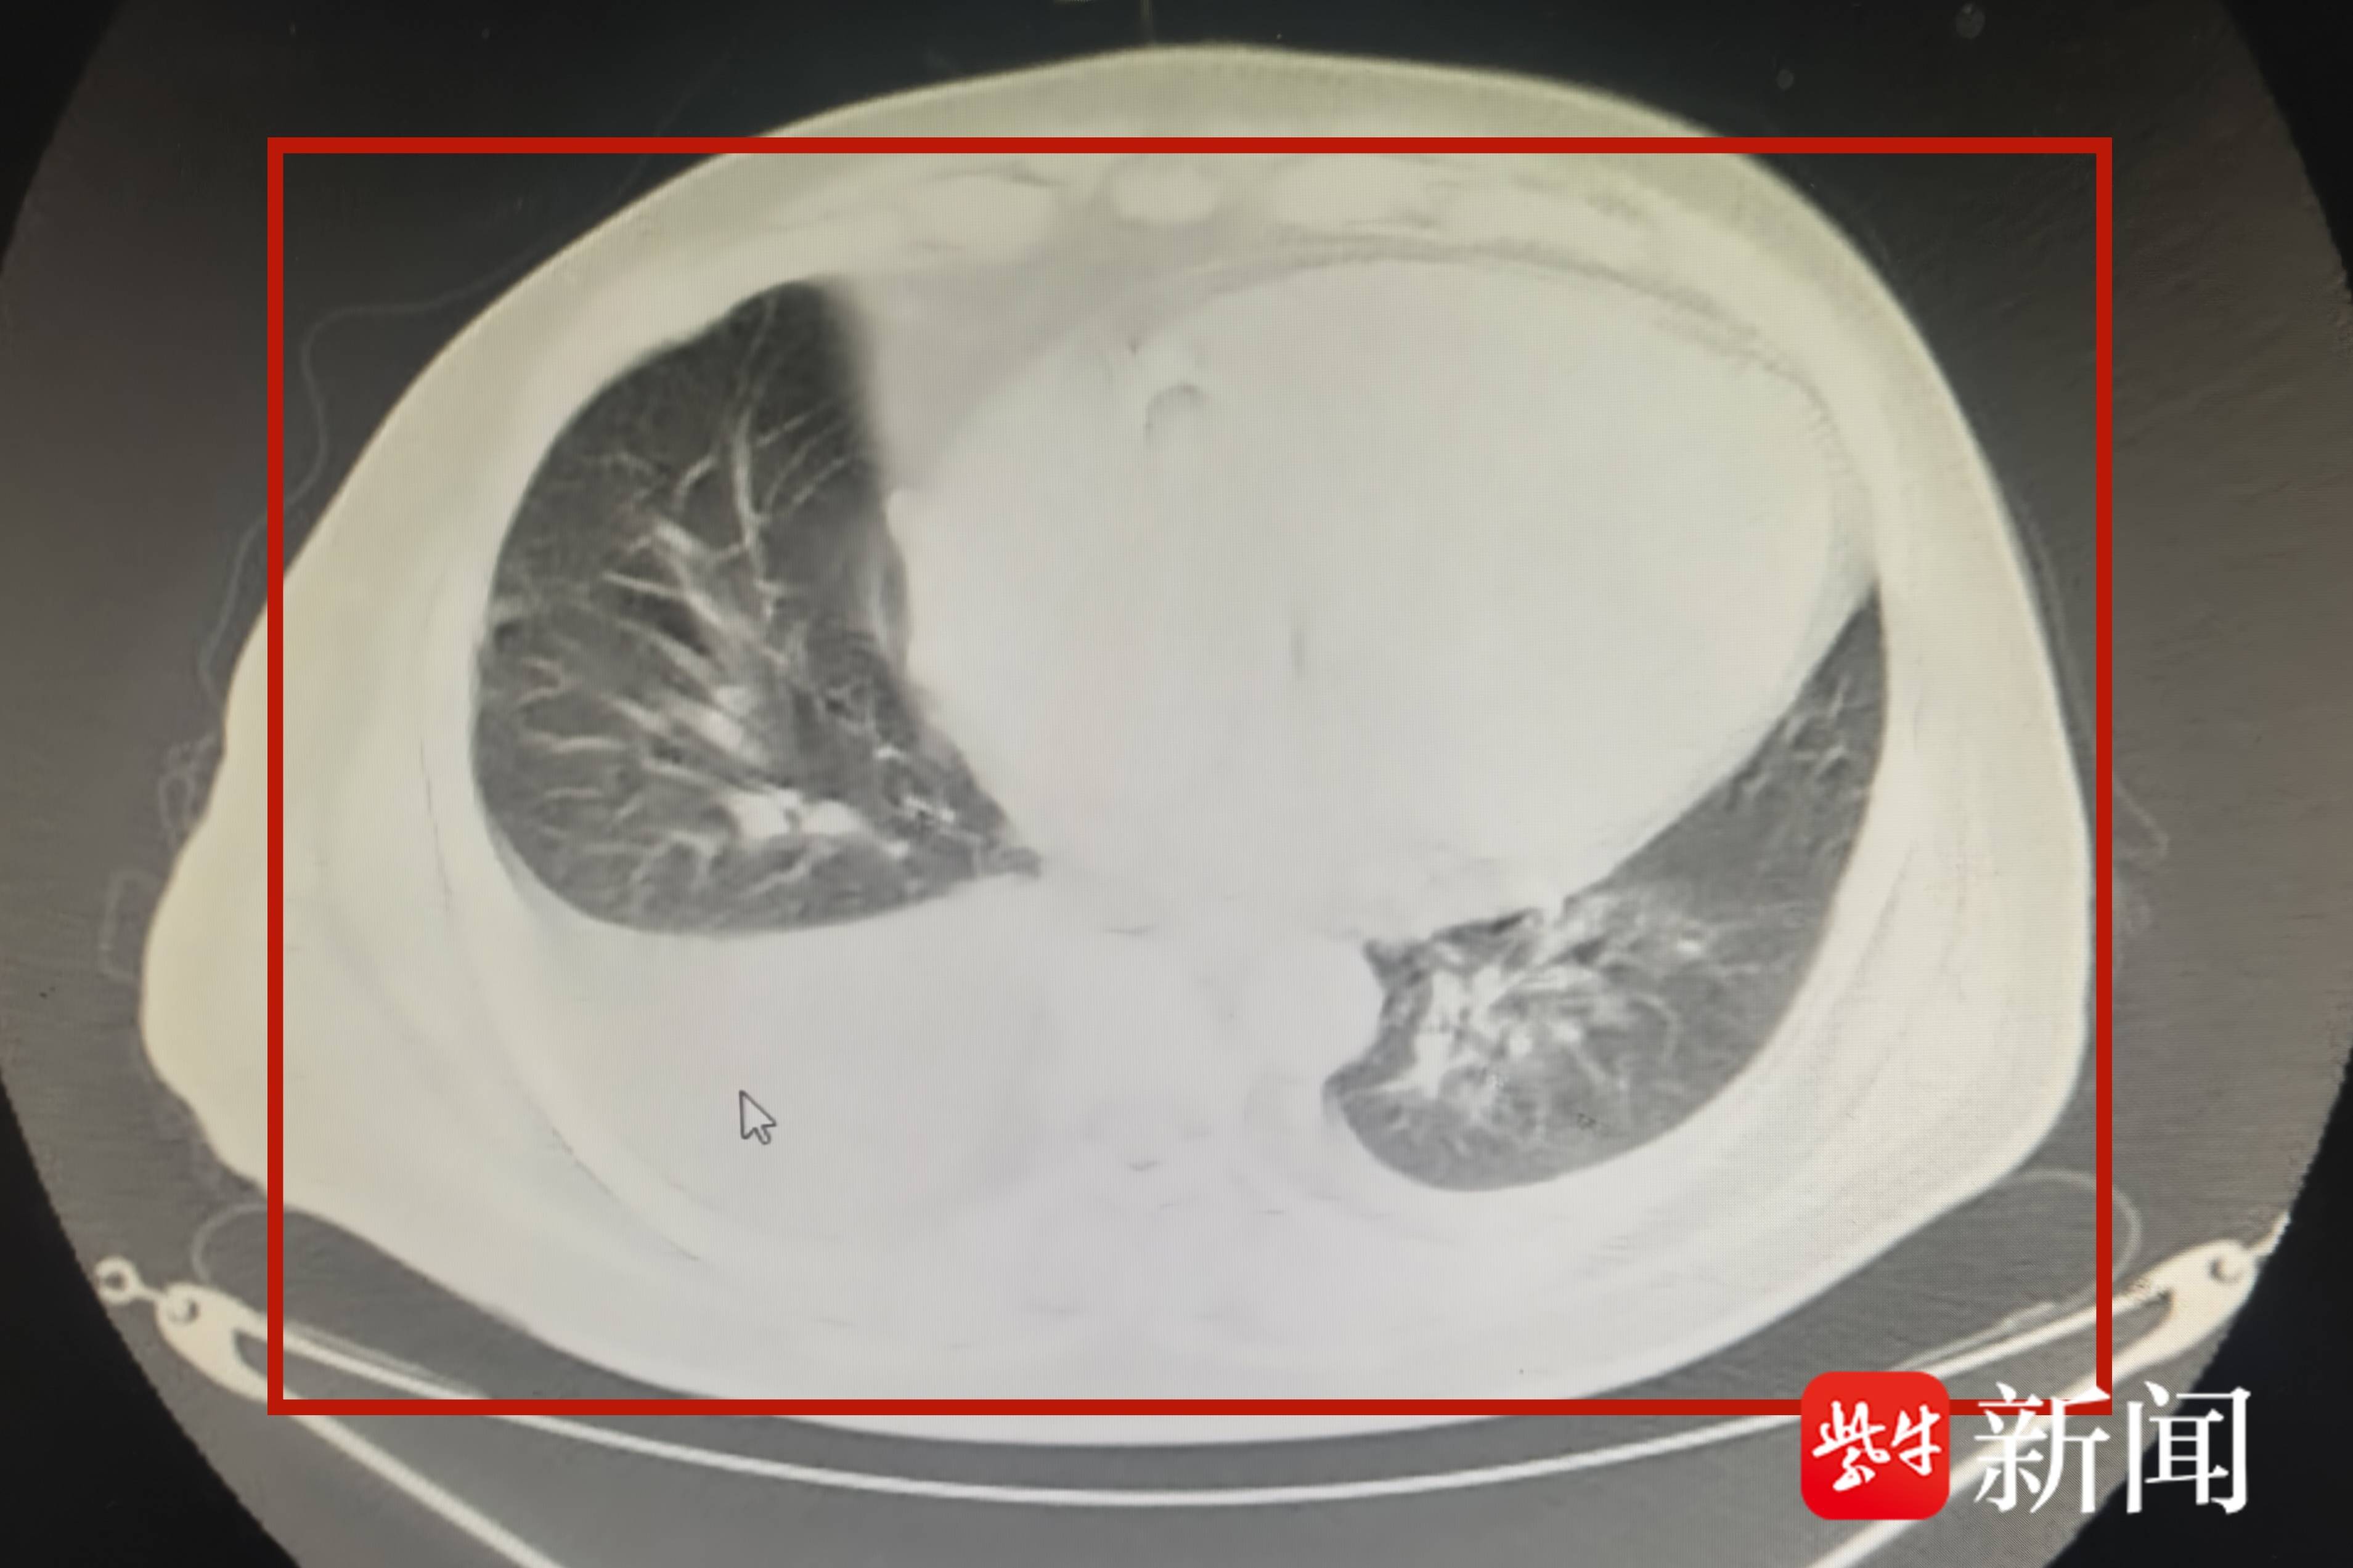

转入肾病科住院时,老董严重气喘、无法行走,由家人用轮椅推入。肾病科副主任中医师胡娟娟检查后发现,患者N端脑利钠肽高达3万多pg/mL,是正常值的120多倍,提示急性心衰。胸部ct和彩超检查显示,患者的胸腔、腹腔积液,连心脏也被“水”淹没了。

影像检查显示,老董的心脏差点被积液“淹没”